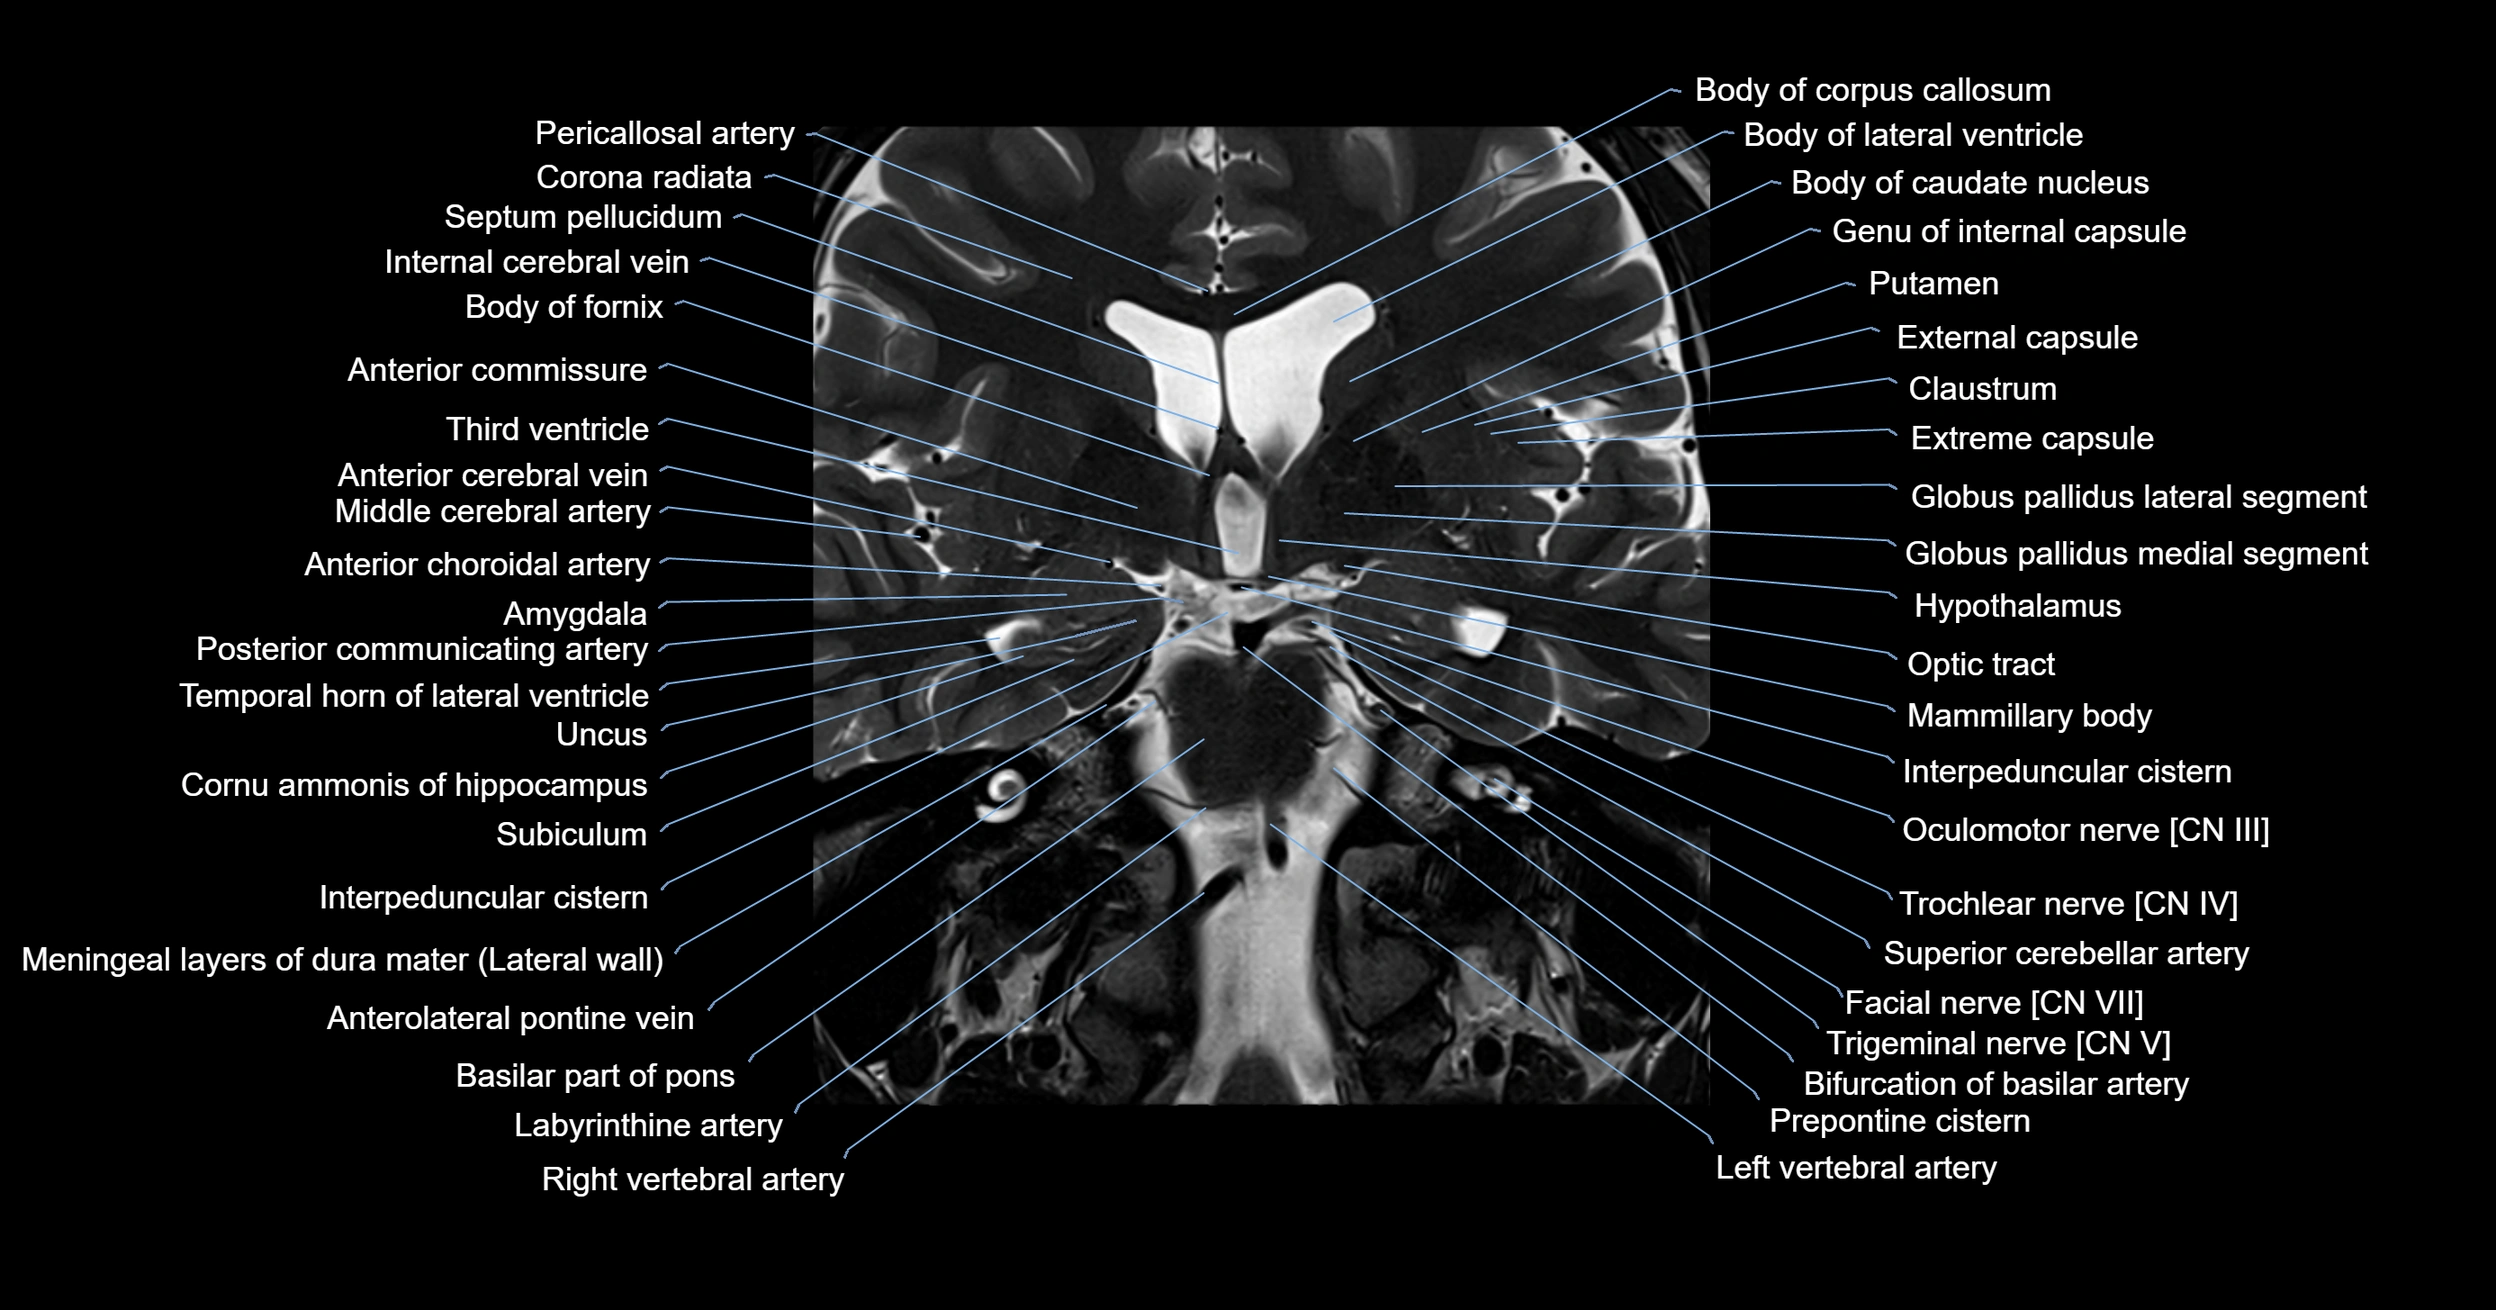

- Amygdala

- Anterior commissure

- Anterolateral pontine vein

- Basilar artery

- Basilar part of pons

- Body of fornix

- Body of lateral ventricle

- Body of corpus callosum

- Corona radiata

- External capsule

- Extreme capsule

- Facial Nerve (Cranial nerve VII)

- Globus pallidus external segment

- Globus pallidus internal segment

- Head of caudate nucleus

- Internal cerebral vein

- Interpeduncular Cistern

- Labyrinthine artery

- Left vertebral artery

- Mammillary body

- Meninges

- Middle cerebral artery

- Oculomotor Nerve (Cranial Nerve III)

- Optic tract

- Posterior communicating artery

- Putamen

- Septum pellucidum

- Superior cerebellar artery

- Temporal horn of lateral ventricle

- Trigeminal nerve (Cranial nerve V)

- Trochlear nerve (Cranial nerve IV)

- Uncus